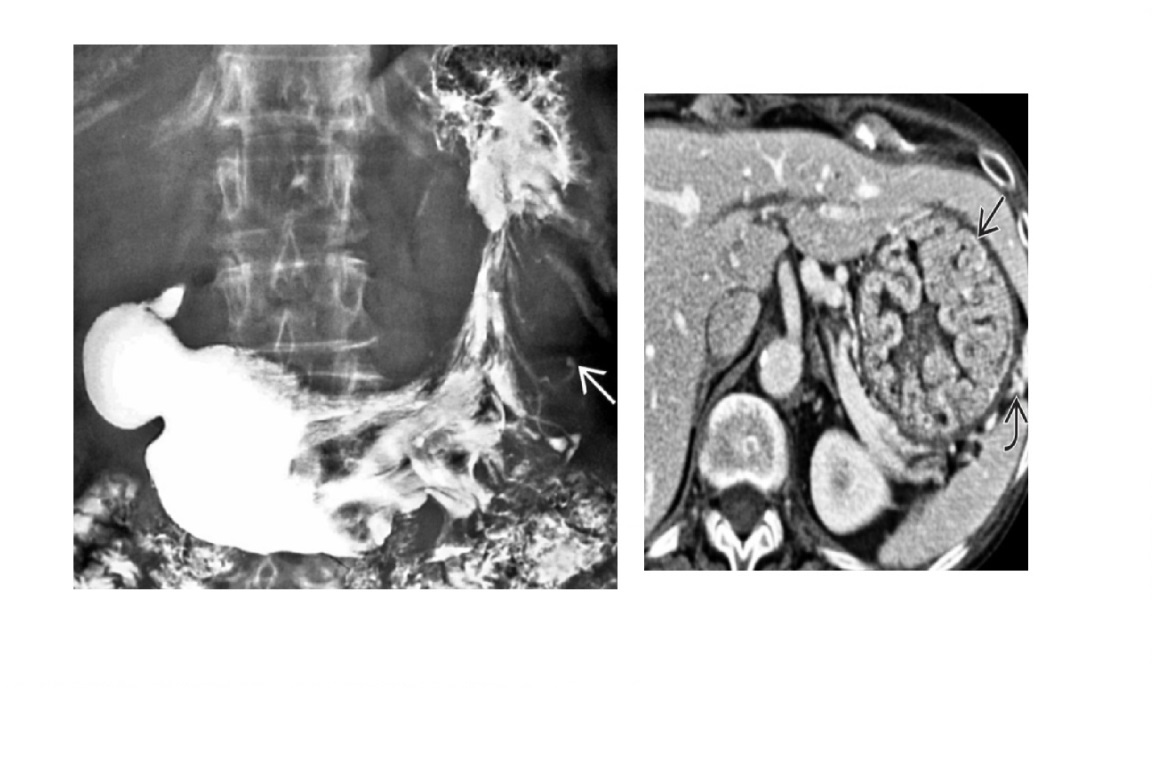

Carcinoid

spiculated mesenteric mass with calcification/ desmoplastic reaction

Tethering of SB loops

90% arise in terminal ileum/appendix

Hyper-vascular liver mets - Carcinoid syndrome

111I- Octreotide scans (1st - highest sensitivity)

or 123I-MIBG (for 10% dont take up octreotide)

for Dx and staging

Big centres use gallium PET

Assocaited with MEN 1 or MEN 2a